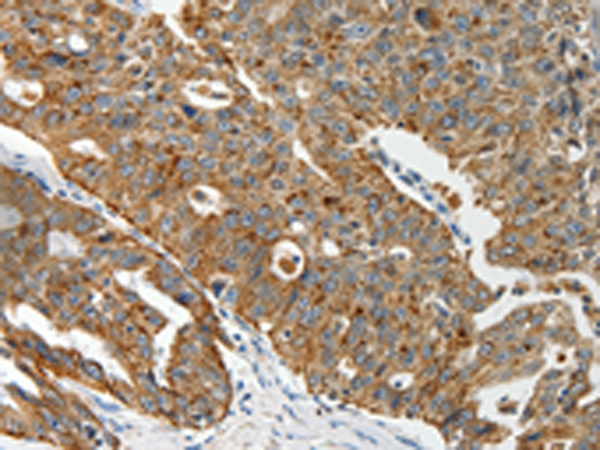

分类: 科研抗体货号: P04245别名: ALDR; ABC39; ALDL1; ALDRP; hALDR应用: IHC反应种属: Human, Mouse, Rat